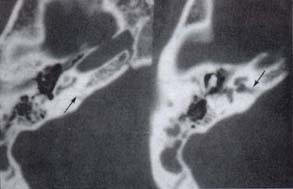

En tomografía computarizada son lesiones expansivas de márgenes bien definidas, con calcificaciones que pueden estar en los epidermoides aunque pueden ser indistinguibles con esta modalidad (Figura 23 a y b).

Figura 23a.Tumor epidermoide

Figura 23b.Tumor epidermoide